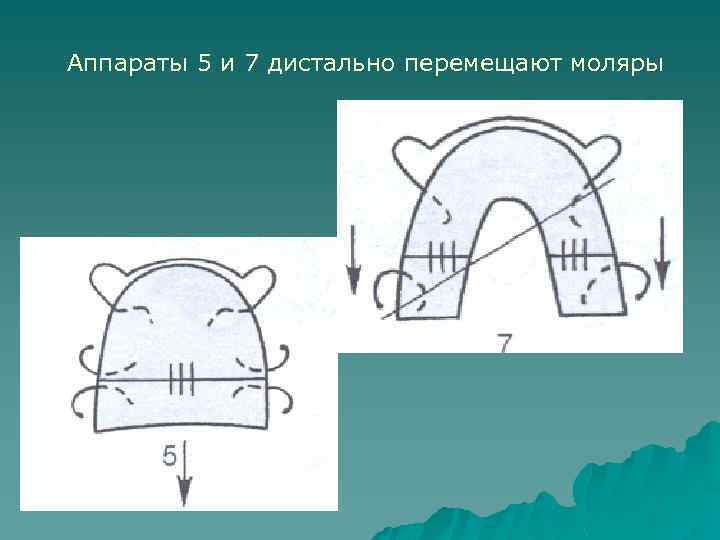

Аппараты 5 и 7 дистально перемещают моляры

Аппарат 6 приводит к дистальному перемещению одного моляра